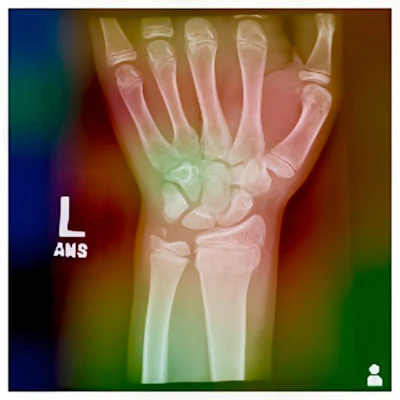

Тепловая карта Grad-CAM модели EfficientNet-B2 для образца рентгенограммы.Журнал Детского ортопедического общества Северной АмерикиСогласно результатам, лучшей моделью оказалась EfficientNet-B2, которая достигла точности валидации 84% и точности тестирования 84% при выявлении переломов эпифизарных зон. Модель продемонстрировала высокую точность (81%), полноту (89%) и оценку F1 (0,86) на тестовом наборе.

Кроме того, для интерпретации прогнозов модели исследователи использовали Grad-CAM — технологию, которая визуализирует области рентгенограмм, на которых модель научилась фокусироваться для классификации.

«Точная настройка модели EfficientNet позволяет добиться высокой точности выявления переломов зон роста. Более того, Grad-CAM обеспечивает интерпретируемость и прозрачность прогнозов модели, выделяя интересующие области и потенциальные источники ошибок», — написала группа.